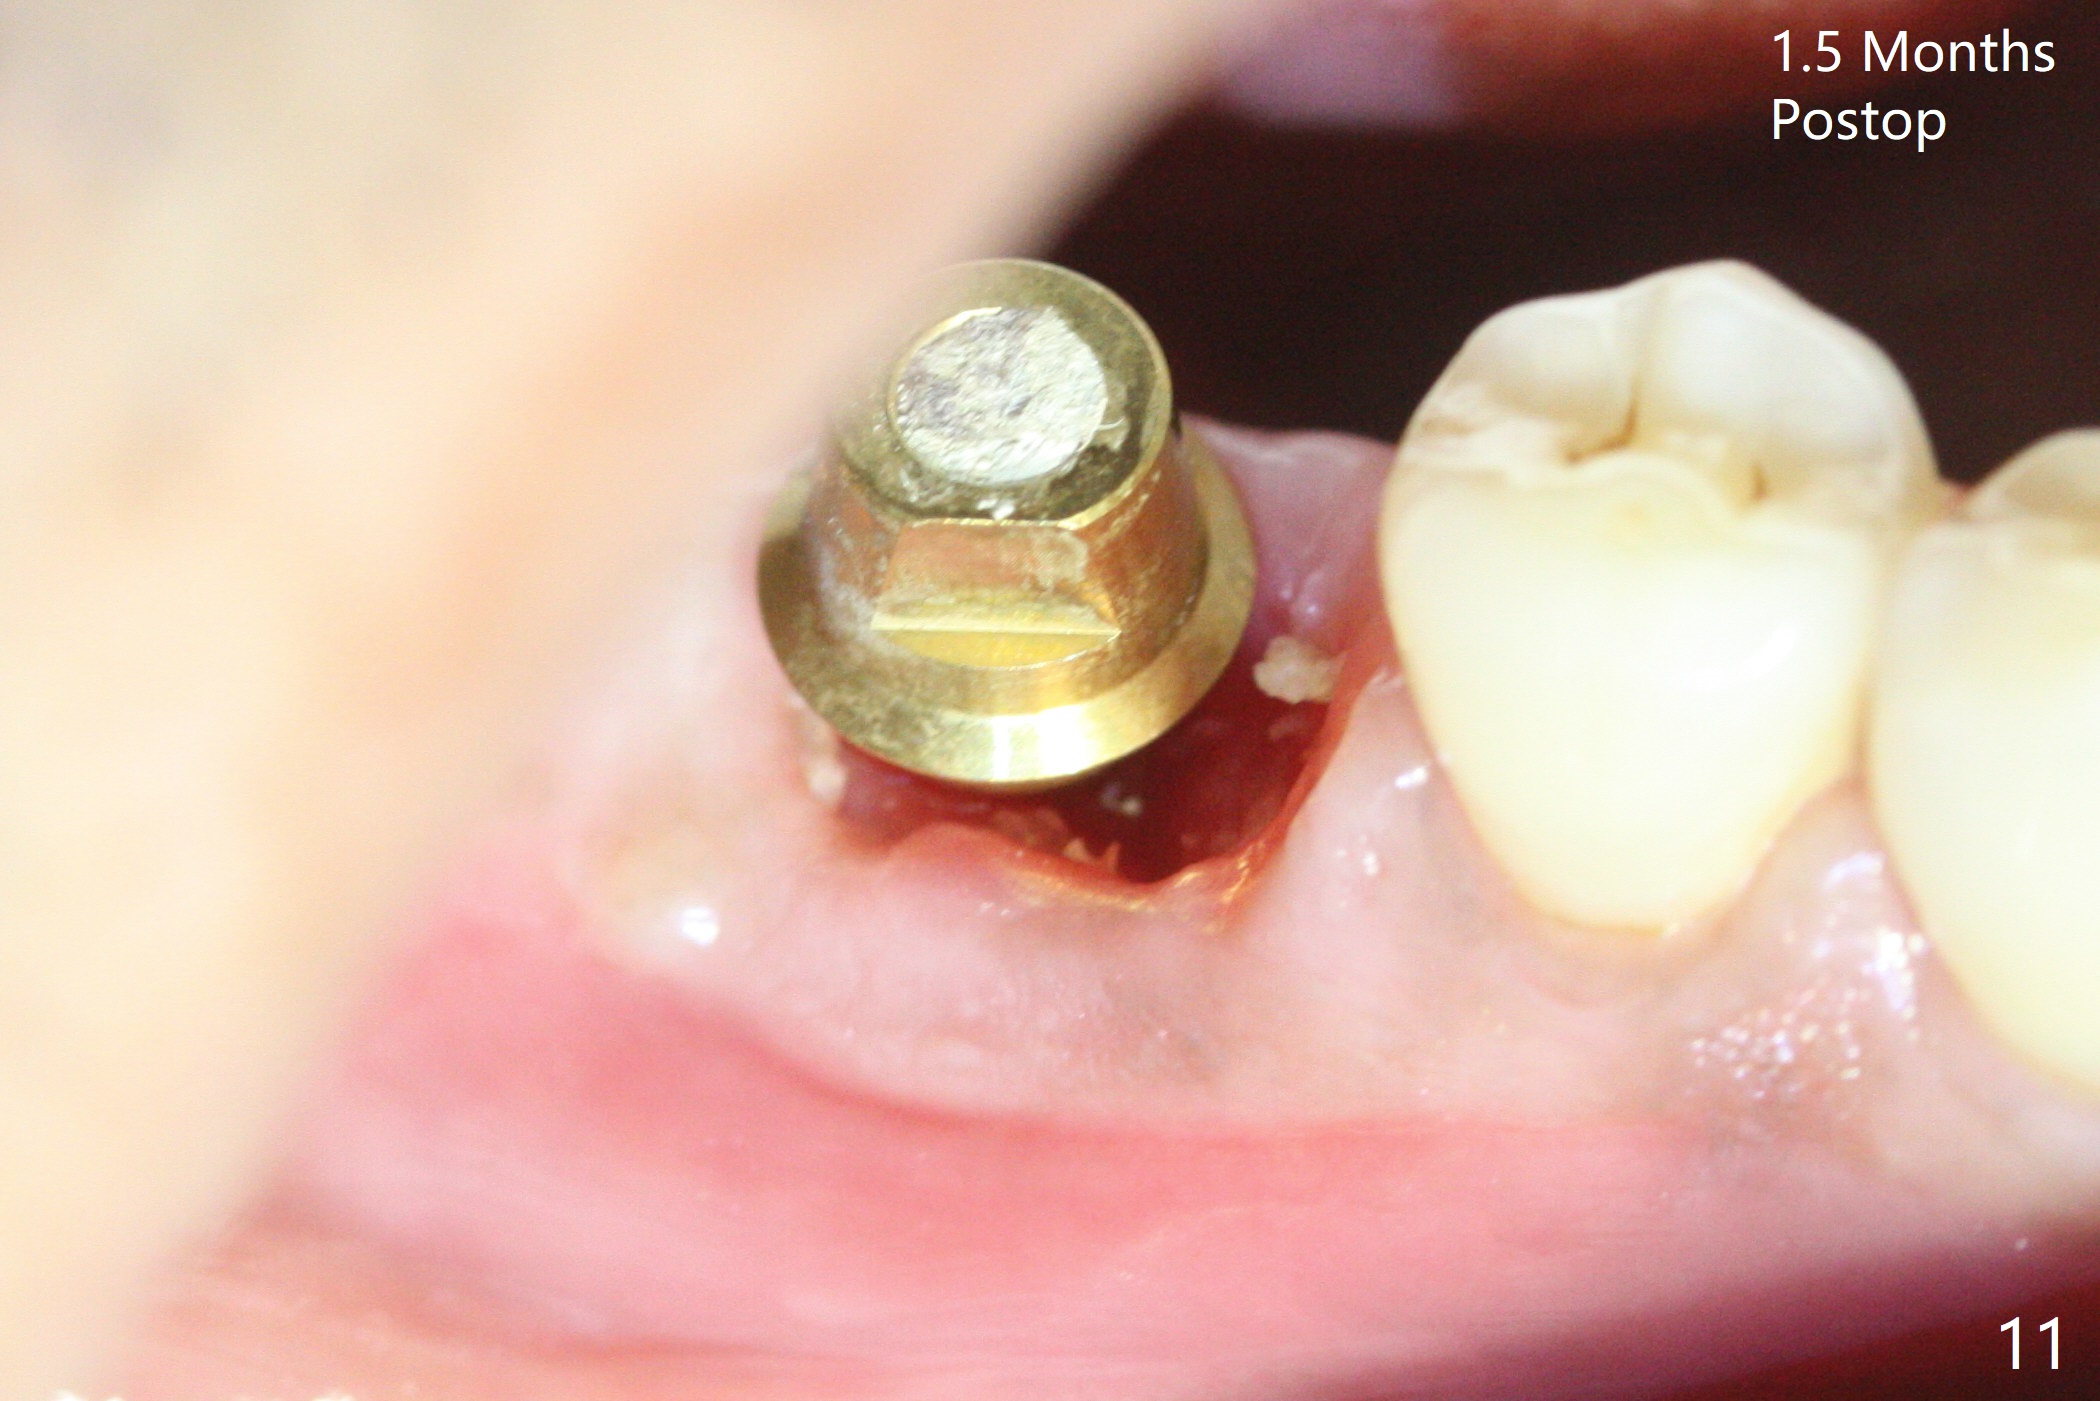

Abutment vs. Definitive One

After extraction of the tooth #30 with lingual subgingival fracture (Fig.1), the septum is fairly large (Fig.2 S). A bony vertical anchor pin (Fig.3 *) is inserted in the septum following pointed drill to to stabilize the guide during osteotomy and implant placement of #31. When the latter is finished, a fixture anchor pin is used at #31 as planned. A healing abutment is placed at #31 because of supraeruption of the tooth #2 (Fig.4,5), while a cementation abutment is placed at #30 (Fig.5) with autogenous bone (from drills) and allograft placed around it (*, Fig.6). Finally an immediate nonfunctional provisional is fabricated to keep the bone graft in place (Fig.7 P). The bone graft remains in place gel-like nearly 1 month postop (Fig.8). CBCT axial section shows that there is not enough space for mini implant placement at the tooth #2 (Fig.9). Restoration-induced intrusion will be conducted using the implants at #30 and 31 three-4 months postop. The buccal gingiva (Fig.10 *) is lingual to the provisional (P) nearly 1.5 months postop. When the provisional is removed, it appears that the mesiobuccal bone graft has lost (Fig.11). Two days later, the cementation abutment is loose and removed; the gingival cuff looks healthy (Fig.12). A 6.8x5 mm healing abutment is placed (Fig.13). In 2.5 to 3 months, abutments will be placed at #30 and 31. Splinted provisional will be fabricated over supraocclusion to intrude the tooth #2 with a stop on the left side. Surprisingly the patient agrees to intrude the tooth #2 with 2 mini implants 5.5 months postop (Fig.14,15). However, the miniimplants dislodged. Due to coronavirus, the implants are restored with heavy abutment and opposing tooth trimming 1 year 9 months postop (Fig.16). Magicore should have been placed instead.